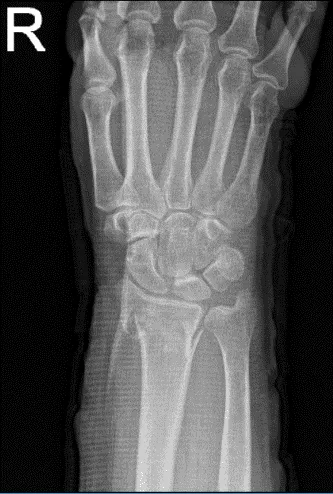

Un paciente de 69 años estaba en nuestra consulta con quejas sobre dolor y deformidad en la muñeca derecha. Allí le pusieron una férula de azúcar y ahora está en Nueva York. Ella sufrió el dolor por la caída. Para los factores agravantes, el paciente informa de empujes/tirones y de carga de peso.

En cuanto a los síntomas asociados, informó de debilidad, hinchazón, sensibilidad al tacto y dolor al moverse, pero no informó entumecimiento, hormigueo, enrojecimiento, calor, equimosis, bloqueo/atrapamiento, chasquido, pandeo, rechinación, inestabilidad, radioterapia, drenaje, fiebre, escalofríos, pérdida de peso y cambios en los hábitos intestinales o urinarios.

El paciente presentó un resultado de resonancia magnética que contenía fractura de Colles con angulación dorsal.

Radiografía de la muñeca derecha 3 o más vistas